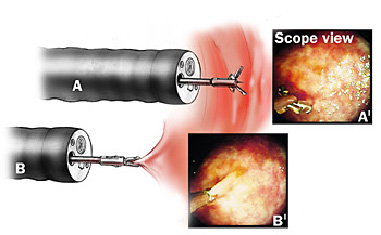

Polipectomia com pinça

Pequenos pólipos podem ser removidos com segurança usando-se apenas uma pinça.

Polipectomia com alça diatérmica

Pólipos maiores necessitam ser removidos com alça e corrente de cauterização. Este procedimento permite cortar a base do pólipo e ao mesmo tempo coagular o local para evitar sangramentos.

Porém alguns pólipos possuem a base (pedículo) largo onde passam vasos calibrosos e por isto tem risco aumentado de sangramento na retirada mesmo usando a corrente de coagulação.

Nestes casos algumas medidas podem ser realizadas para diminuir o risco de sangramento:

Injeção de adrenalina na base do pólipo

Colocação de um laço na base do pólipo para estrangular o pedículo

Alguns pólipos são tão grandes que não podem ser removidos inteiros. Nestes casos o pólipo é retirado em pedaços para poder garantir a sua remoção completa.

Alguns pólipos não possuem a base alongada (pedículo), estes são chamados de pólipos sésseis. A remoção destes pólipos possui risco maior de perfuração do órgão pois como são planos ficam muito próximos da parede externa do órgão.

Mucosectomia

Para diminuir este risco, injeta-se com um uma agulha uma solução abaixo do pólipo para que ele levante e fique mais longe da parede do órgão. Após isto passa-se a alça diatérmica e realiza-se o

procedimento de polipectomia.